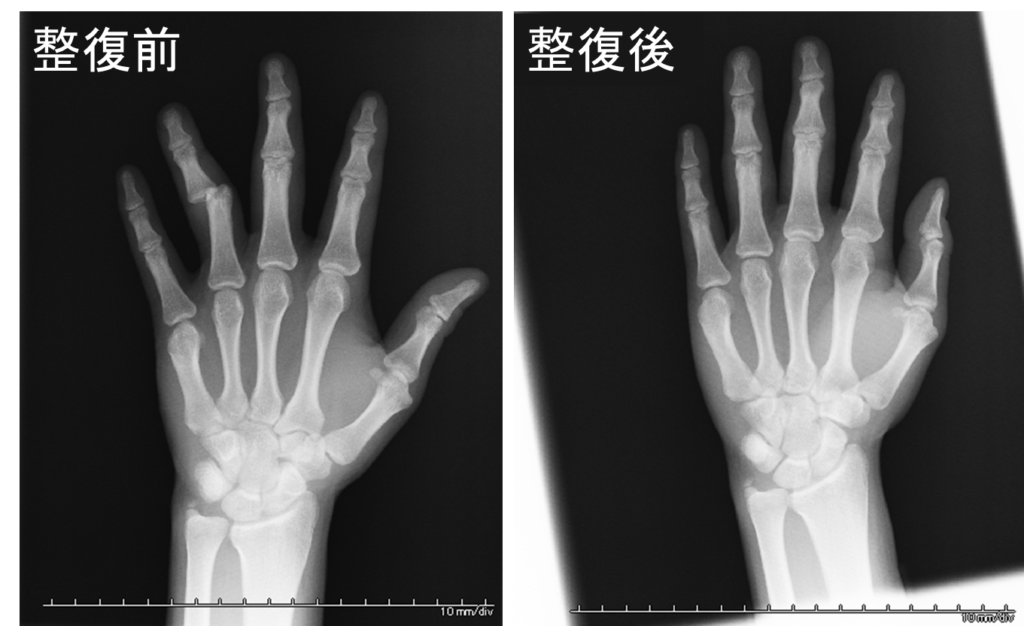

症例2)20歳男子大学生、飲酒時に高椅子から転倒した際に、床に手を衝いて転倒したが、直後は痛みを感じずそのまま帰宅。深夜徐々に痛みが増強し、レントゲン検査の結果、左第4指近位指節間関節不全脱臼、柔道整復を施し処置は見事に成功。1週間ほどの固定後、温熱療法やマッサージで元の機能に戻す治療を行いました。

レントゲンをはじめて見る人には少しショッキングかもしれませんが、